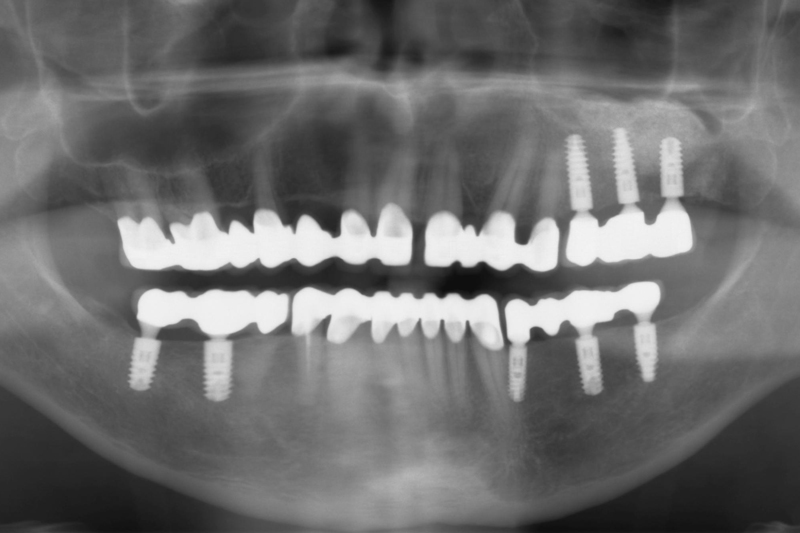

Uzupełnienie zębów przy obustronnych brakach skrzydłowych w szczęce i żuchwie mostami stałymi, opartymi na implantach i zębach własnych oraz poprawa estetyki zębów przednich koronami pełnoceramicznymi.

- Radiologiczny obraz kliniczny po zakończonej terapii